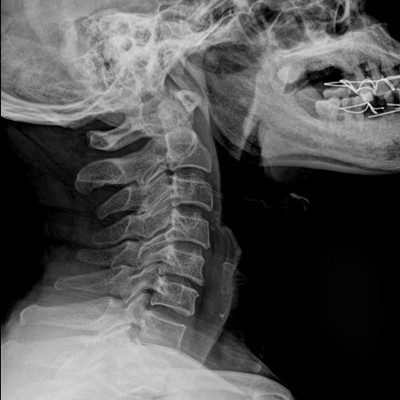

高品質影像鏈 讓您看的更清晰 PLX8500C/D

●大尺寸非晶硅平板探測器。

●非晶硅平板探測器,采用先進的制造工藝、性能更穩定。

●探測器可以大范圍轉動,大尺寸有效探測面積,可滿足人體多部位攝影需求。